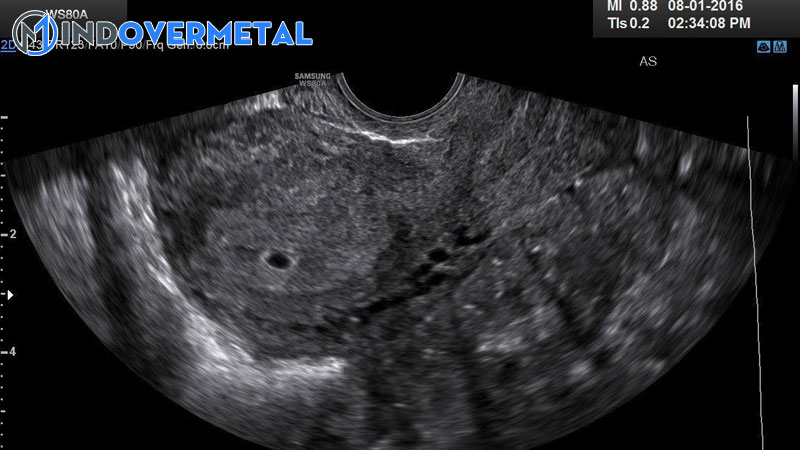

Việc siêu âm có túi thai nhưng chưa thấy phôi thai ở tuần thứ 5 là thông thường, bác sĩ sẽ khuyên mẹ nghỉ ngơi khoảng chừng 1-2 tuần rồi kiểm tra tiếp hoặc ngay khi có những bộc lộ không bình thường như ra huyết, đau bụng. Tùy từng hiệu quả siêu âm kiểm tra lại, nếu vẫn chưa có phôi thai, bác sĩ sẽ tìm nguyên do và cho mẹ giải pháp hài hòa và hợp lý nhất

Việc siêu âm có túi thai nhưng chưa thấy phôi thai ở tuần thứ 5 là thông thường ( Ảnh minh họa )